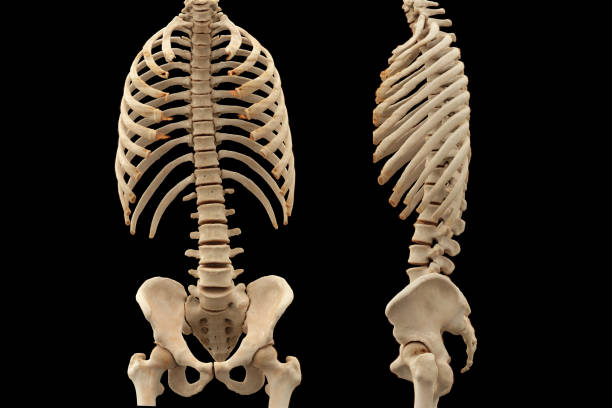

요추 염좌의 원인은 비만, 무리한 운동, 자세 등 다양한 요인과 관련이 있으므로 건강한 생활 습관과 적절한 운동이 필요합니다.

요약하면, 허리 통증과 요추염좌는 일상생활에서 흔히 겪을 수 있는 문제이며, 적절한 치료와 예방을 통해 건강한 척추를 유지하는 것이 중요합니다. 만약 통증이 심하다면 전문의의 도움을 받아보는 것이 좋습니다.